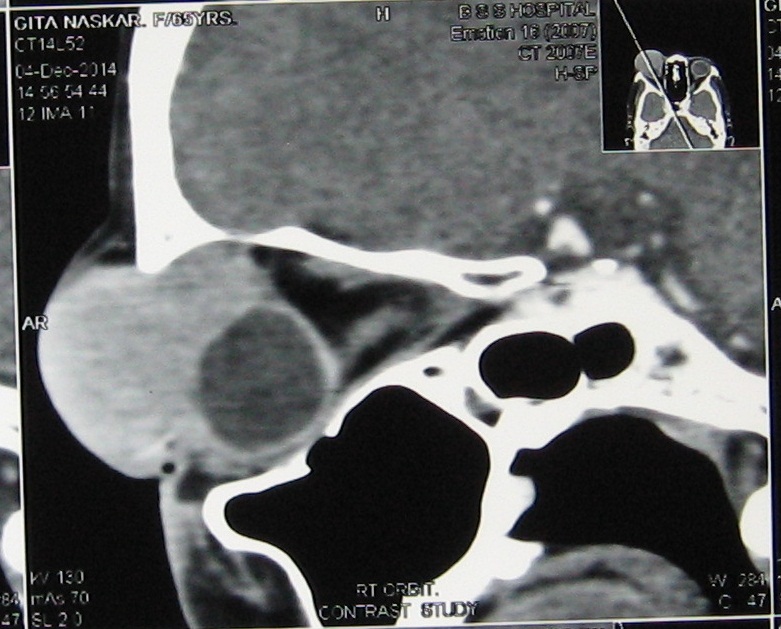

Primary Non-Hodgkins lymphoma of the orbit is a rare presentation and the diffuse large B-cell lymphoma (DLCL) type of histology is much less commoner than the mucosa associated lymphoid tissue (MALT) and follicular lymphoma. A 70 years female patient presented with palpable mass arising from right orbit and proptosis of the right eye. CT scan suggested homogenous enhancing soft tissue mass affecting right lacrimal region without any bony destruction. Biopsy confirmed it to be a case of Primary non-Hodgkins lymphoma of diffuse large B-cell type with strongly positive CD 20. She was given 6 cycles of chemotherapy with R-CHOP after surgery. The patient is now asymptomatic one year after the last cycle of the chemotherapy.